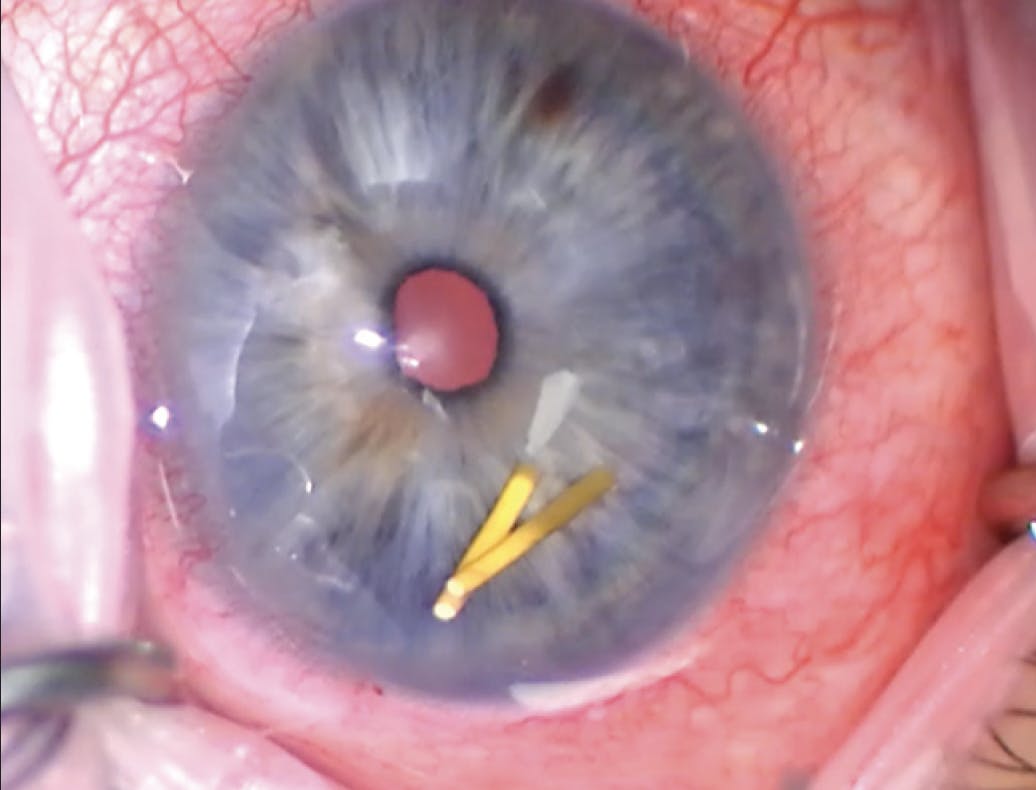

Upon presentation, the patient’s BCVA is 20/20 OU. His IOP is 23 mm Hg OD and 12 mm Hg OS. An examination of each eye finds a deep, quiet anterior chamber; a well-centered posterior chamber IOL in the capsular bag; and slight pseudophacodonesis. Gonioscopy shows grade 4 angles with a yellow cylindrical foreign body in the inferior angle of the right eye (Figure 1). A fundus examination finds optic nerve cupping bilaterally that is greater in the right eye and classic findings of birdshot chorioretinopathy (Figure 2).

On the day of surgery, I examined the patient once he was in a supine position. To my surprise, two implants were visible in the angle (Figure 5). I created a clear corneal incision and removed the implants (watch the video below). I then rotated my hand and performed an approximately 180º goniotomy enhancement with a straight Sinskey hook. I accessed the inferior angle through a superior incision. During the procedure, I visualized and removed a membrane that had covered the previous goniotomy site, resulting in good blood reflux (Figure 6).

Figure 5. Surgical image of two fluocinolone acetonide intravitreal implants in the anterior chamber before removal.